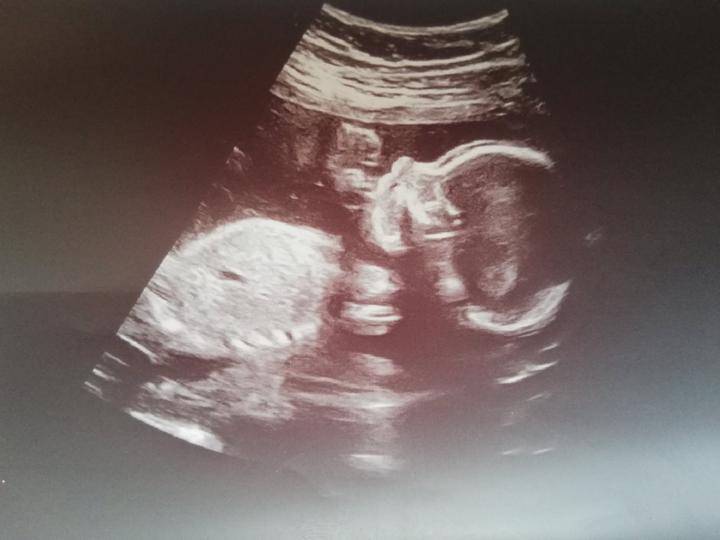

Tak ahoj, dneska jsme absolvovali velky utz a je to HOLČIČKA 😍😍😀 je zdravá a váží cca 450g, zivala a curala 😁😁 úplně živá, od dost vic než jsme takhle viděli našeho prvního😁😊takže máme páreček a přítel měl opět pravdu, že to bude to pohlaví které řekl při pohledu na první těhotenský test. 😍